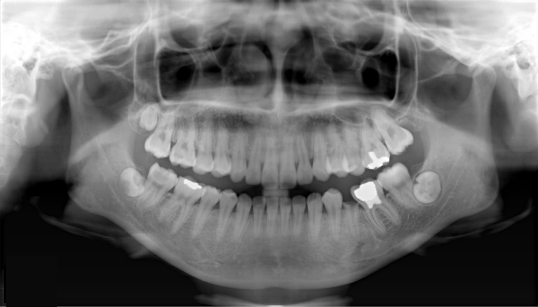

Встала я под аппарат

он вокруг меня покружился и получился снимок ВСЕХ зубов с корнями, даже пазухи носа )))Так прикольно было смотреть... Мне все рассказали, показали... В восторге была!Покажу пример из инета:

Я знала, что проблемы есть, но чтобы так и столько!!!

Ужас! Кариес почти всех жев.зубов (((